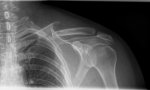

Pues acabo de llegar de hacerme la radiografía compañeros.

Os pongo la de hace 2 semanas y la de hoy que hace 4 semanas.

Yo no entiendo mucho y no quiero hacerme ilusiones,pero el cambio es bastante a mejor…

Menos acortamiento ,los huesos juntos “menos uno de minuta” que tengo la esperanza que también soldaría,pero a ver que me dice el trauma el Jueves que esta vez si que voy informado y no me muevo de la silla sin diagnóstico.

Yo creo que lo que se han juntado bastante en 2 semanas sólo es buena señal no?.

Porque que estén juntos es que han empezado a pegar?

En la primera RX estaban un pelin separados.

No sabría qué decirte. No veo mucho avance.

Por cierto, las costillas qué tal? Te duelen?

Ostras…

Pues yo veo mucho en sólo dos semanas…

De estar separados por unos 2-3mm está ya junto por más 5mm y el acortamiento es menor.

Mira…

Esta es de las dos semanas…

En la flecha que señalo se ve que estaban separados 2-3mm y en el triángulo rojo también se aprecia el desplazamiento hacia arriba.